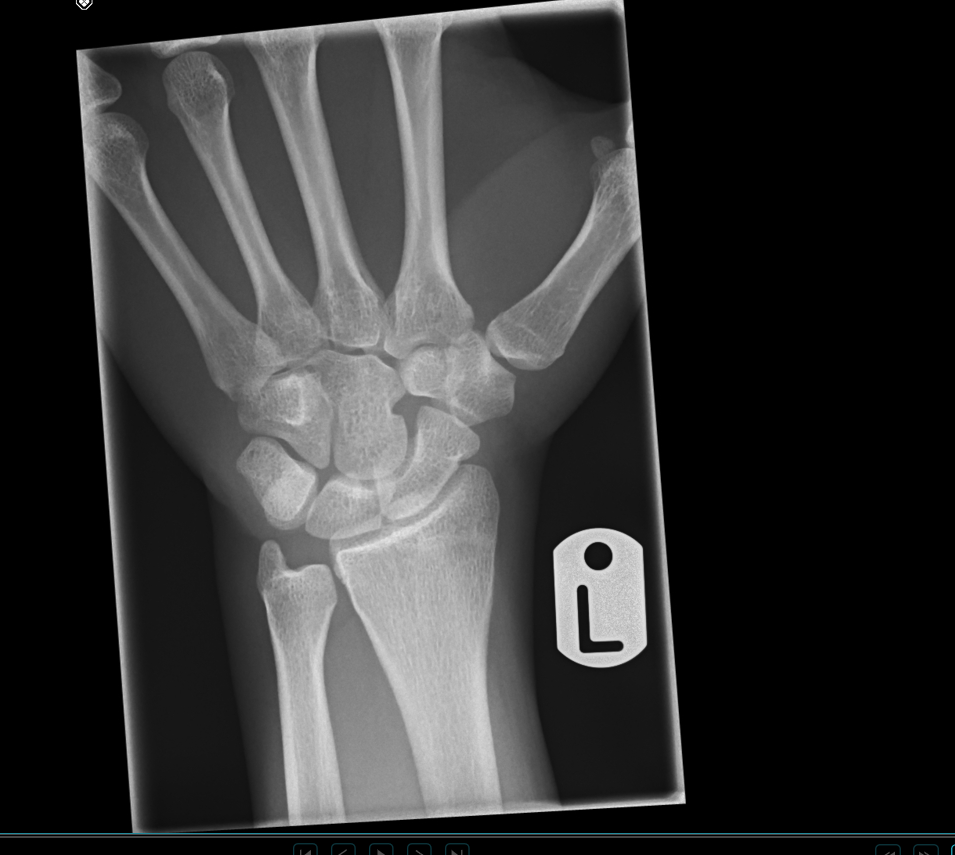

Attached is an image of my left wrist, my plates appear fully fused, so its likely over for me, no point in hopping on gh. I've heard the gp responsible for your height growth close later, such as those in the knee- but I'm probably gonna be a manlet forever. Quite disappointing because i had uncles growing massively after 18 to 195cm, a taller mother who was also a late bloomer, and felt like i had a later puberty myself (e.g at 17 i still have barely any armpit hair) but i guess i was wrong